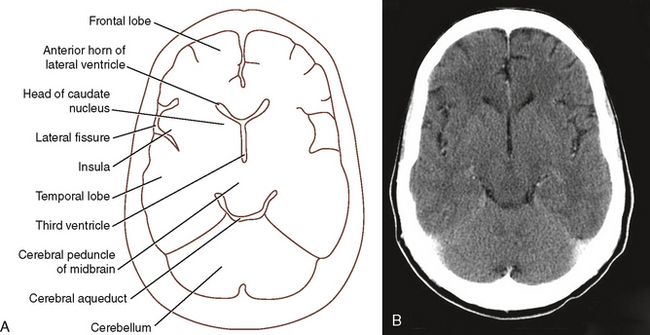

Sectional Anatomy For Radiographers Radiology Key

Sectional Anatomy For Radiographers Radiology Key

Sectional Anatomy For Radiographers Radiology Key

Sectional Anatomy For Radiographers Radiology Key

Sectional Anatomy For Radiographers Radiology Key

Sectional Anatomy For Radiographers Radiology Key